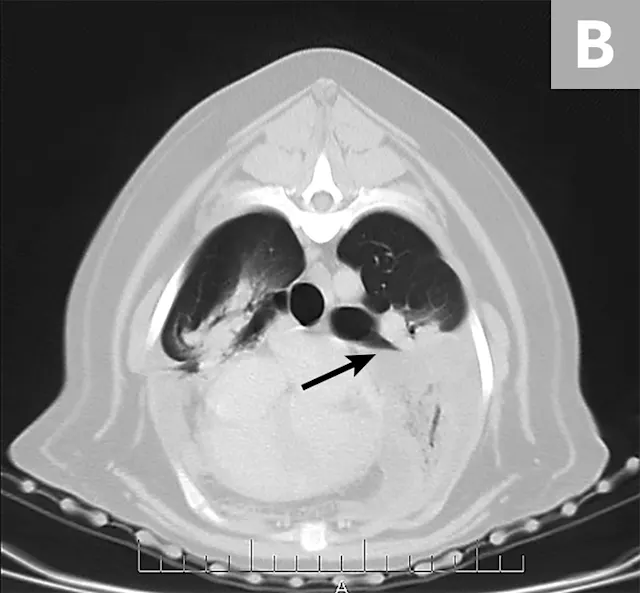

Radiographs obtained after thoracocentesis demonstrated improved pleural effusion and consolidation of the left middle lung lobe (Figure 3). Based on the soft tissue bulge near the hilum and the air bronchocram extending cranially, the primary differential was lung lobe torsion (LLT). Other considerations included pulmonary mass, abscess, or granuloma.

FIGURE 3A

Right lateral (A) and ventrodorsal (B) thoracic radiographs obtained after thoracocentesis showing improvement in pleural effusion with a persistent soft tissue opacity in the left mid-to-cranial thorax. An air bronchogram is seen extending cranially from the hilus (arrowhead) where a subtle bulge (arrow) is present.